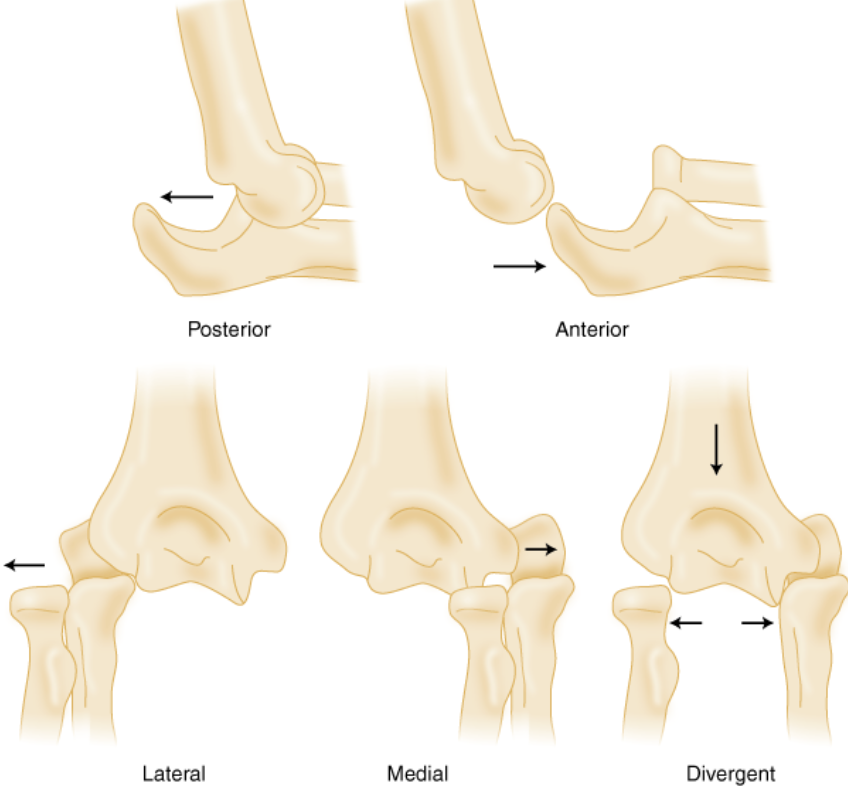

How to reduce elbow dislocation. Normal alignment after the elbow has been reduced. On the other hand, some dislocations may not. Be careful on slippery surfaces and stairs to avoid falls.

Caution can help reduce your risk of a dislocated elbow. The act of restoring alignment to the elbow is called a reduction maneuver. Types of reduction of elbow dislocation first aid immediately after the injury you should put.

Sedation and muscle relaxers may be necessary to correct your elbow dislocation. This clip describes why elbow dislocation is hard to achieve in dogs, but when it occurs, how it is reduced. What are the risk factors for.